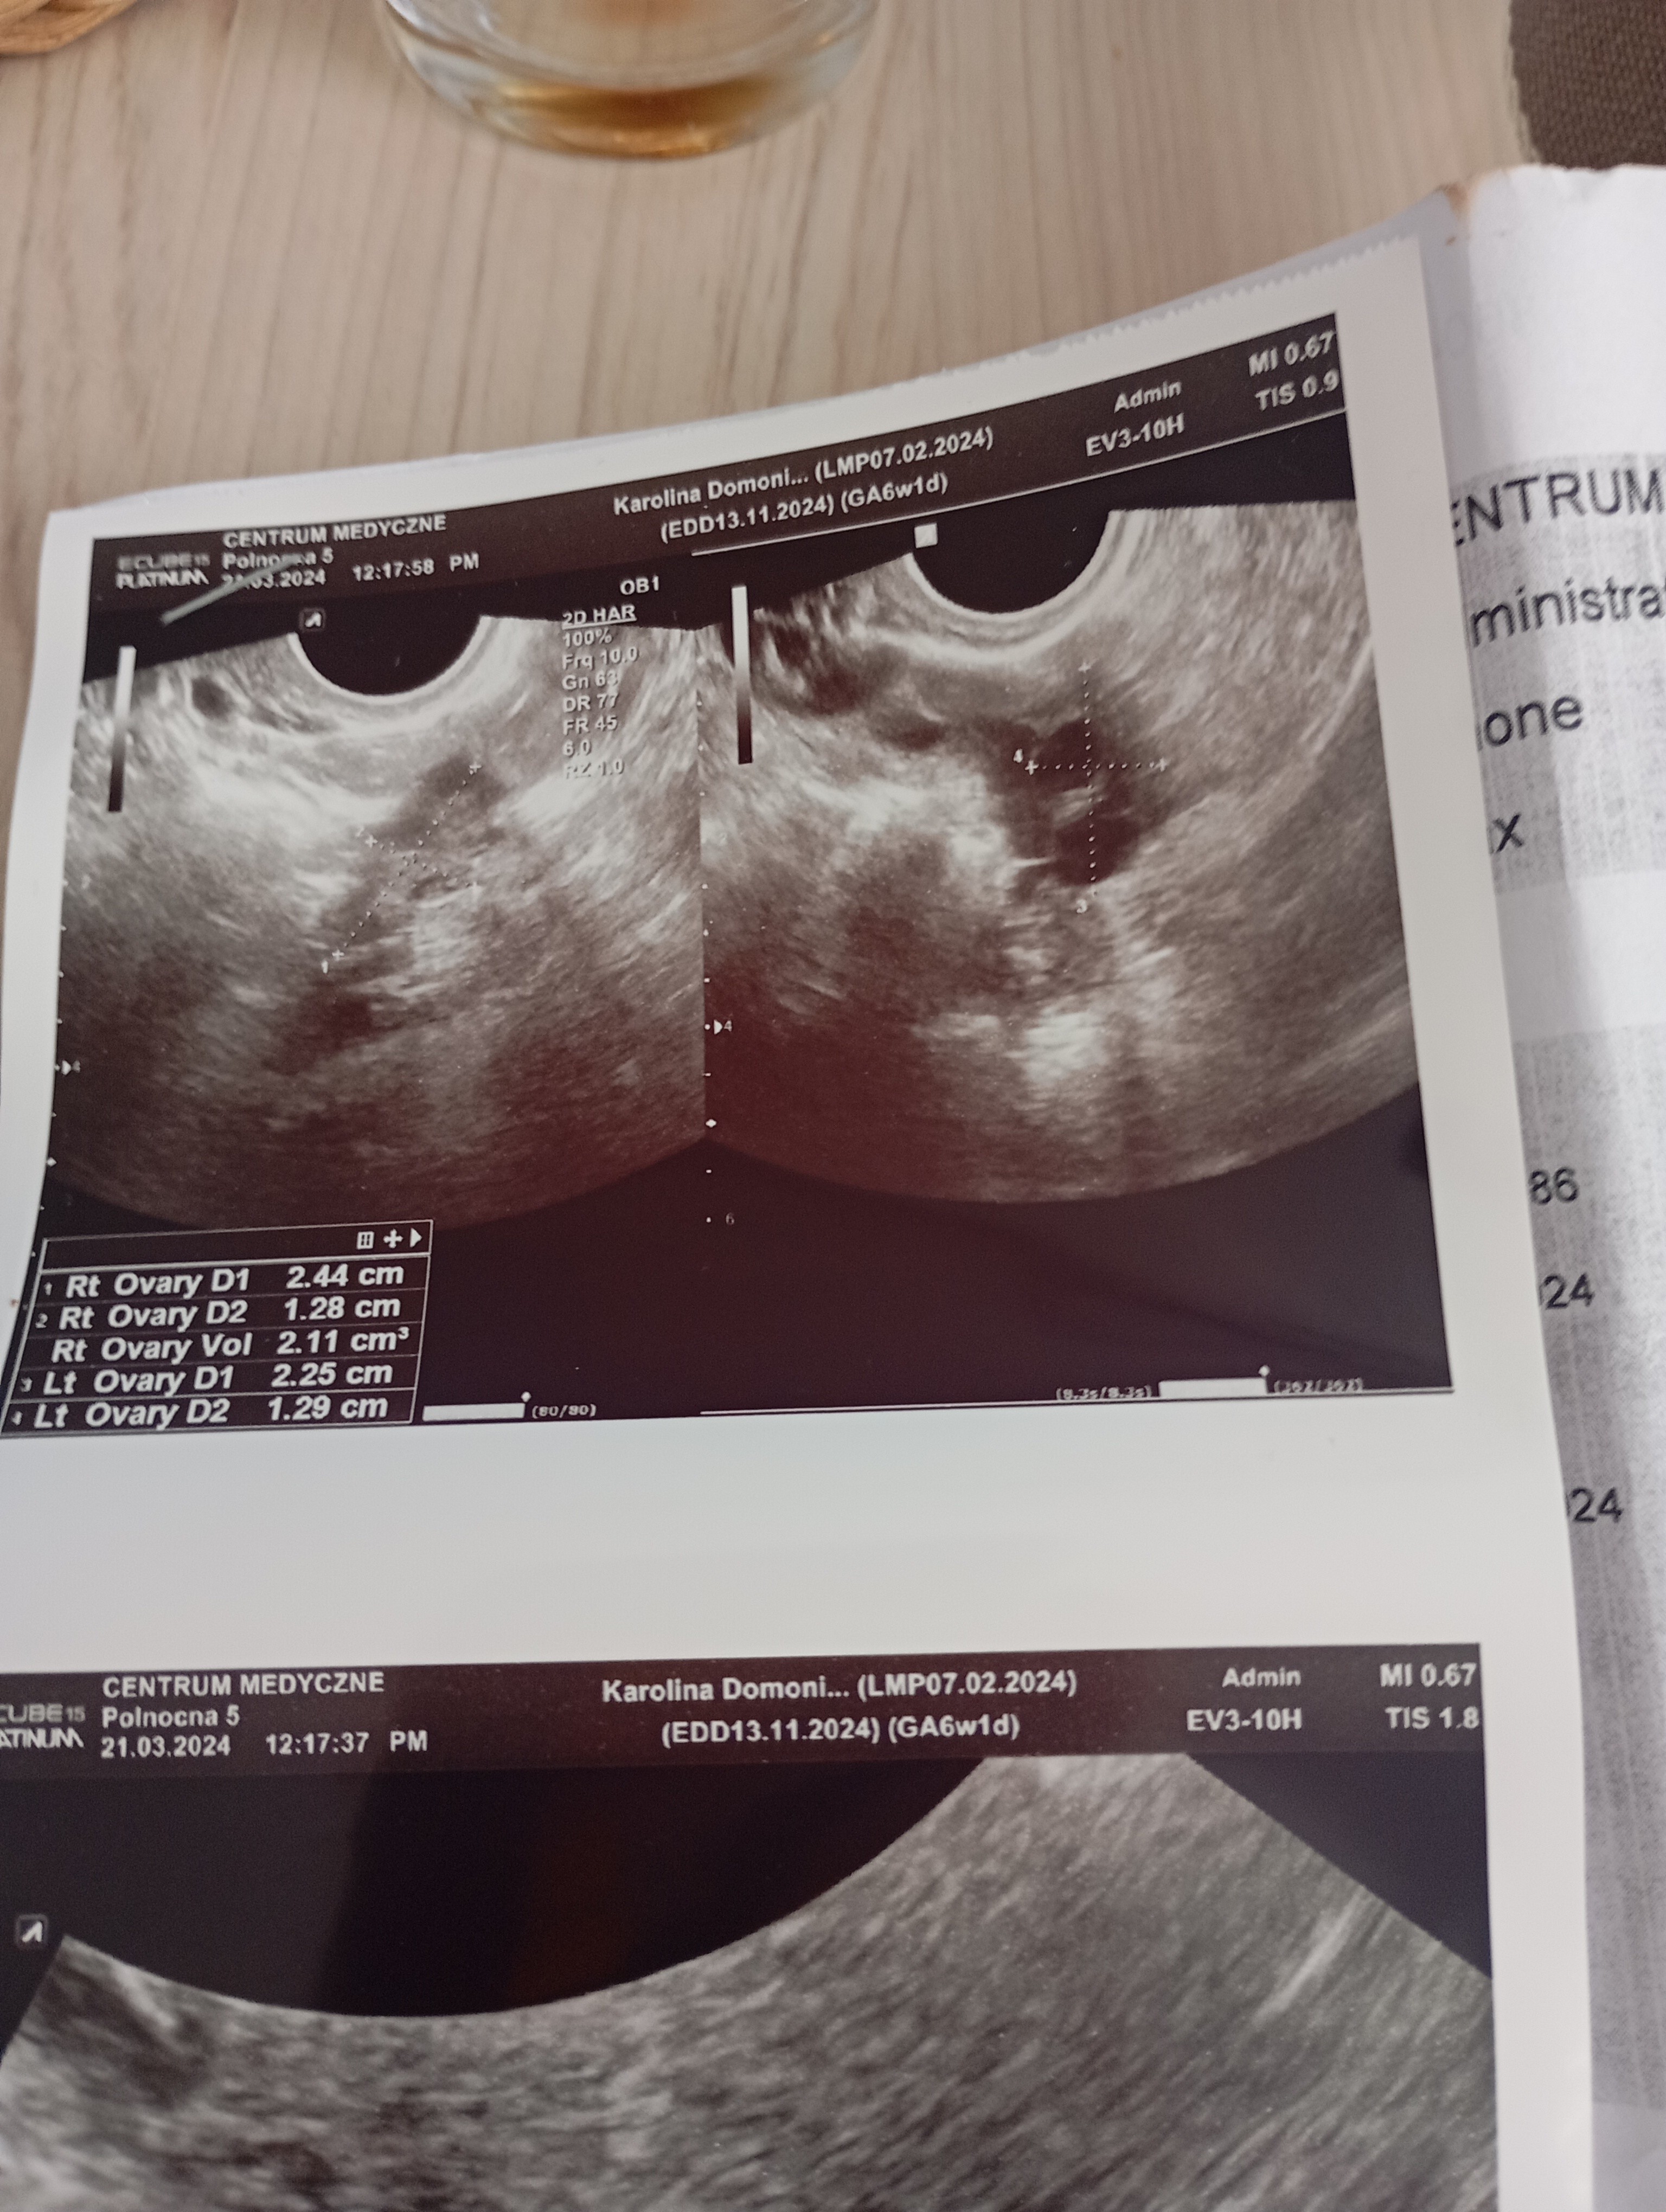

Część dziewczyny. Właśnie wróciłam od lekarza . Na USG nie widać zarodka. Strasznie nie miła lekarz nie chciała nic mówić. Kazała przyjść za tydzień i zleciła luteinę. Beta ładnie rośnie. Czy ktoś się na tym zna ?

• IMG_20240321_142521.jpg

IMG_20240321_142521.jpg

1,8 MB · Wyświetleń: 554

• IMG_20240321_142523.jpg

IMG_20240321_142523.jpg

1,8 MB · Wyświetleń: 219

• IMG_20240321_142525.jpg

IMG_20240321_142525.jpg

1,9 MB · Wyświetleń: 225